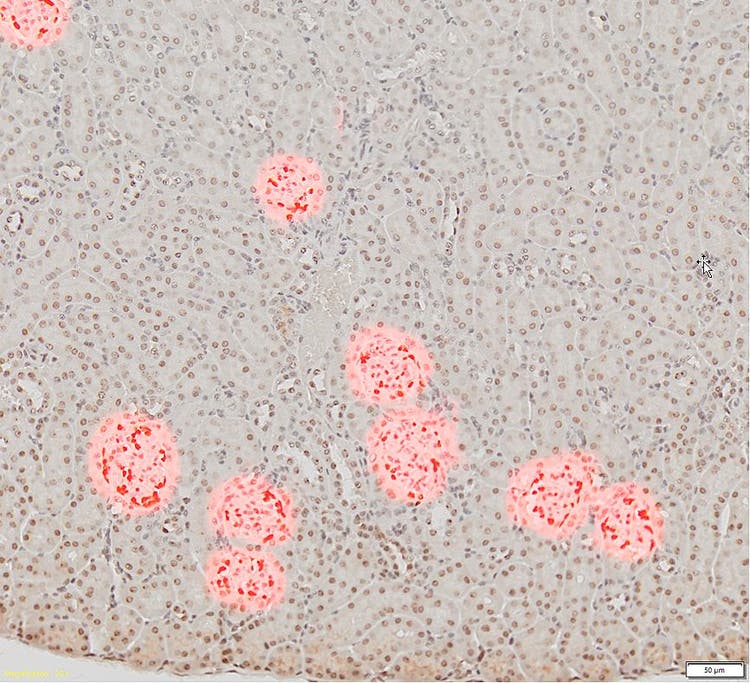

Lame (à gauche) d’une coupe de tissu rénal (grossissement x20) avec glomérules marqués apparaissant en marron foncé et lame (à droite) (grossissement x10) illustrant l’échec de la détection par la méthode de détection par seuil conventionnelle (en rouge) des cellules glomérulaires par rapport aux autres cellules présentes dans le tissu

Image reproduite avec l’aimable autorisation de Zhenhua Miao, scientifique principal à ChemoCentryx, Inc. Mountain View, Californie, États-Unis)

Habituellement, lorsqu’ils analysent ces structures à partir d’images numériques, les chercheurs sélectionnent manuellement les glomérules, ce qui prend beaucoup de temps. De plus, les méthodes traditionnelles de segmentation automatique, telles que les algorithmes basés sur des seuils, ne permettent pas de détecter exclusivement les glomérules, comme l’illustre la figure ci-dessus.